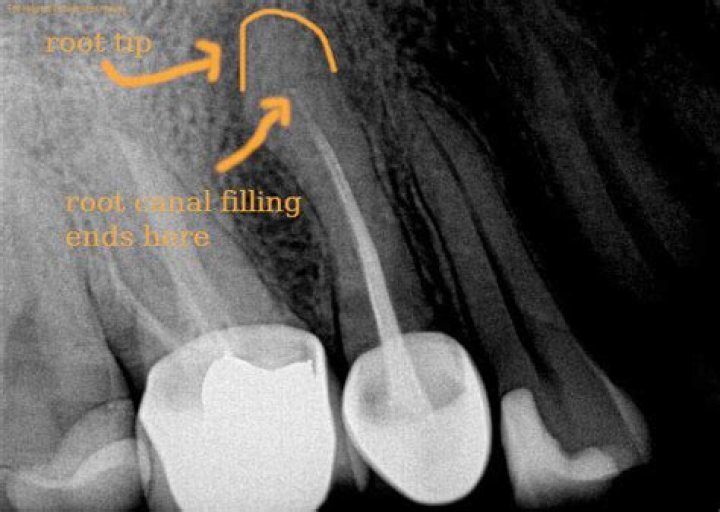

While root canal treatment takes place on the crown of the tooth (the part above the gum that we chew with) an apicoectomy takes place on the root of the tooth. The infected tissue is accessed via the root tip, also called the apex, of the tooth, and a filling is then placed to seal the end of the root.